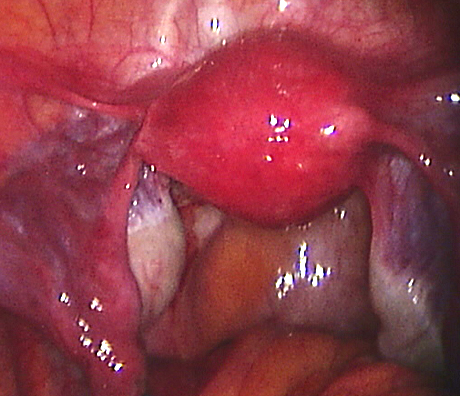

Endometriosis is a non-cancerous condition where the endometrial tissue or womb lining which normally grows only in the uterus is found in other parts of your pelvis, for example the ovaries, fallopian tubes, rectum, bladder, appendix and pelvic walls. This womb lining that grows outside the uterus responds also to hormones but at the time of your periods it can not be expelled (as the womb lining) and causes pain, cysts in the ovaries (called chocolate cysts), inflammation in your pelvis, scar tissue, pain with sexual intercourse, chronic pelvic pain, pain when passing bowel motions, lower backache, symptoms similar to urinary tract infections, premenstrual discomfort, etc.

Laparoscopy is an operation (keyhole surgery) conducted under general anaesthesia. A telescope is introduced into a small incision in your navel, other small incisions are made for using special laparoscopic instruments and all the pelvic organs are examined with magnification (Video-laparoscopy) ; then the endometriosis is treated. Video Laparoscopy allows conservative surgery (hysterectomy is NOT the usual treatment for endometriosis) which means laparoscopic excision of the endometriotic implants, with restoration of the normal anatomy and preservation of the uterus, tubes and ovaries.